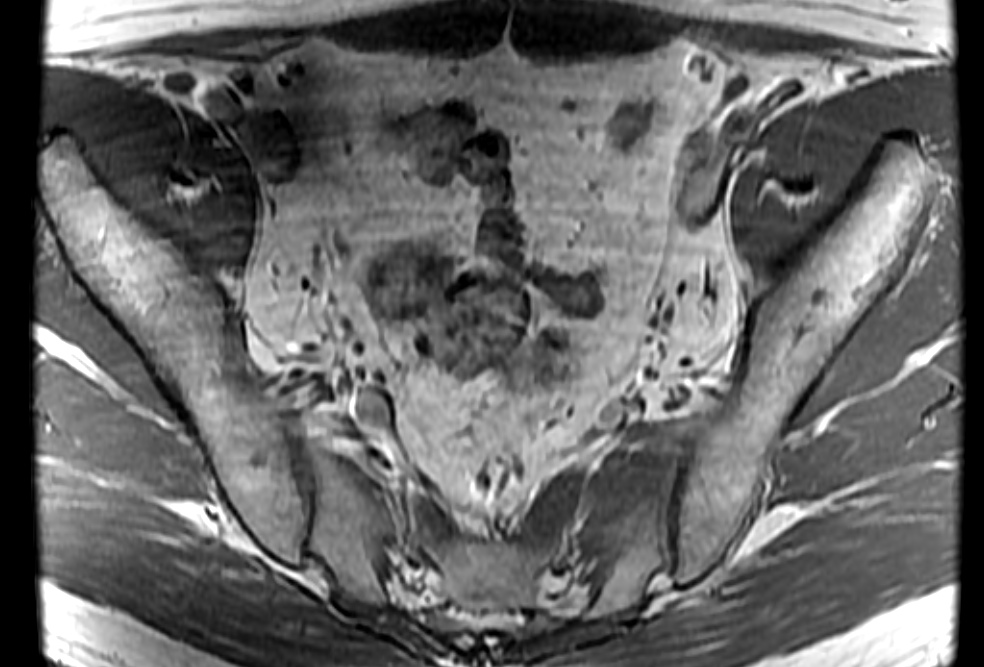

Bilateral accessory piriformis muscles at the S2 level attaching to the sacral body, anterior the S2 nerve roots. Normal piriformis muscles should be posterior to the sacral nerve roots. The result is that the S2 nerve roots may be pinched between the piriformis and accessory piriformis muscles.

Bilateral accessory piriformis muscles